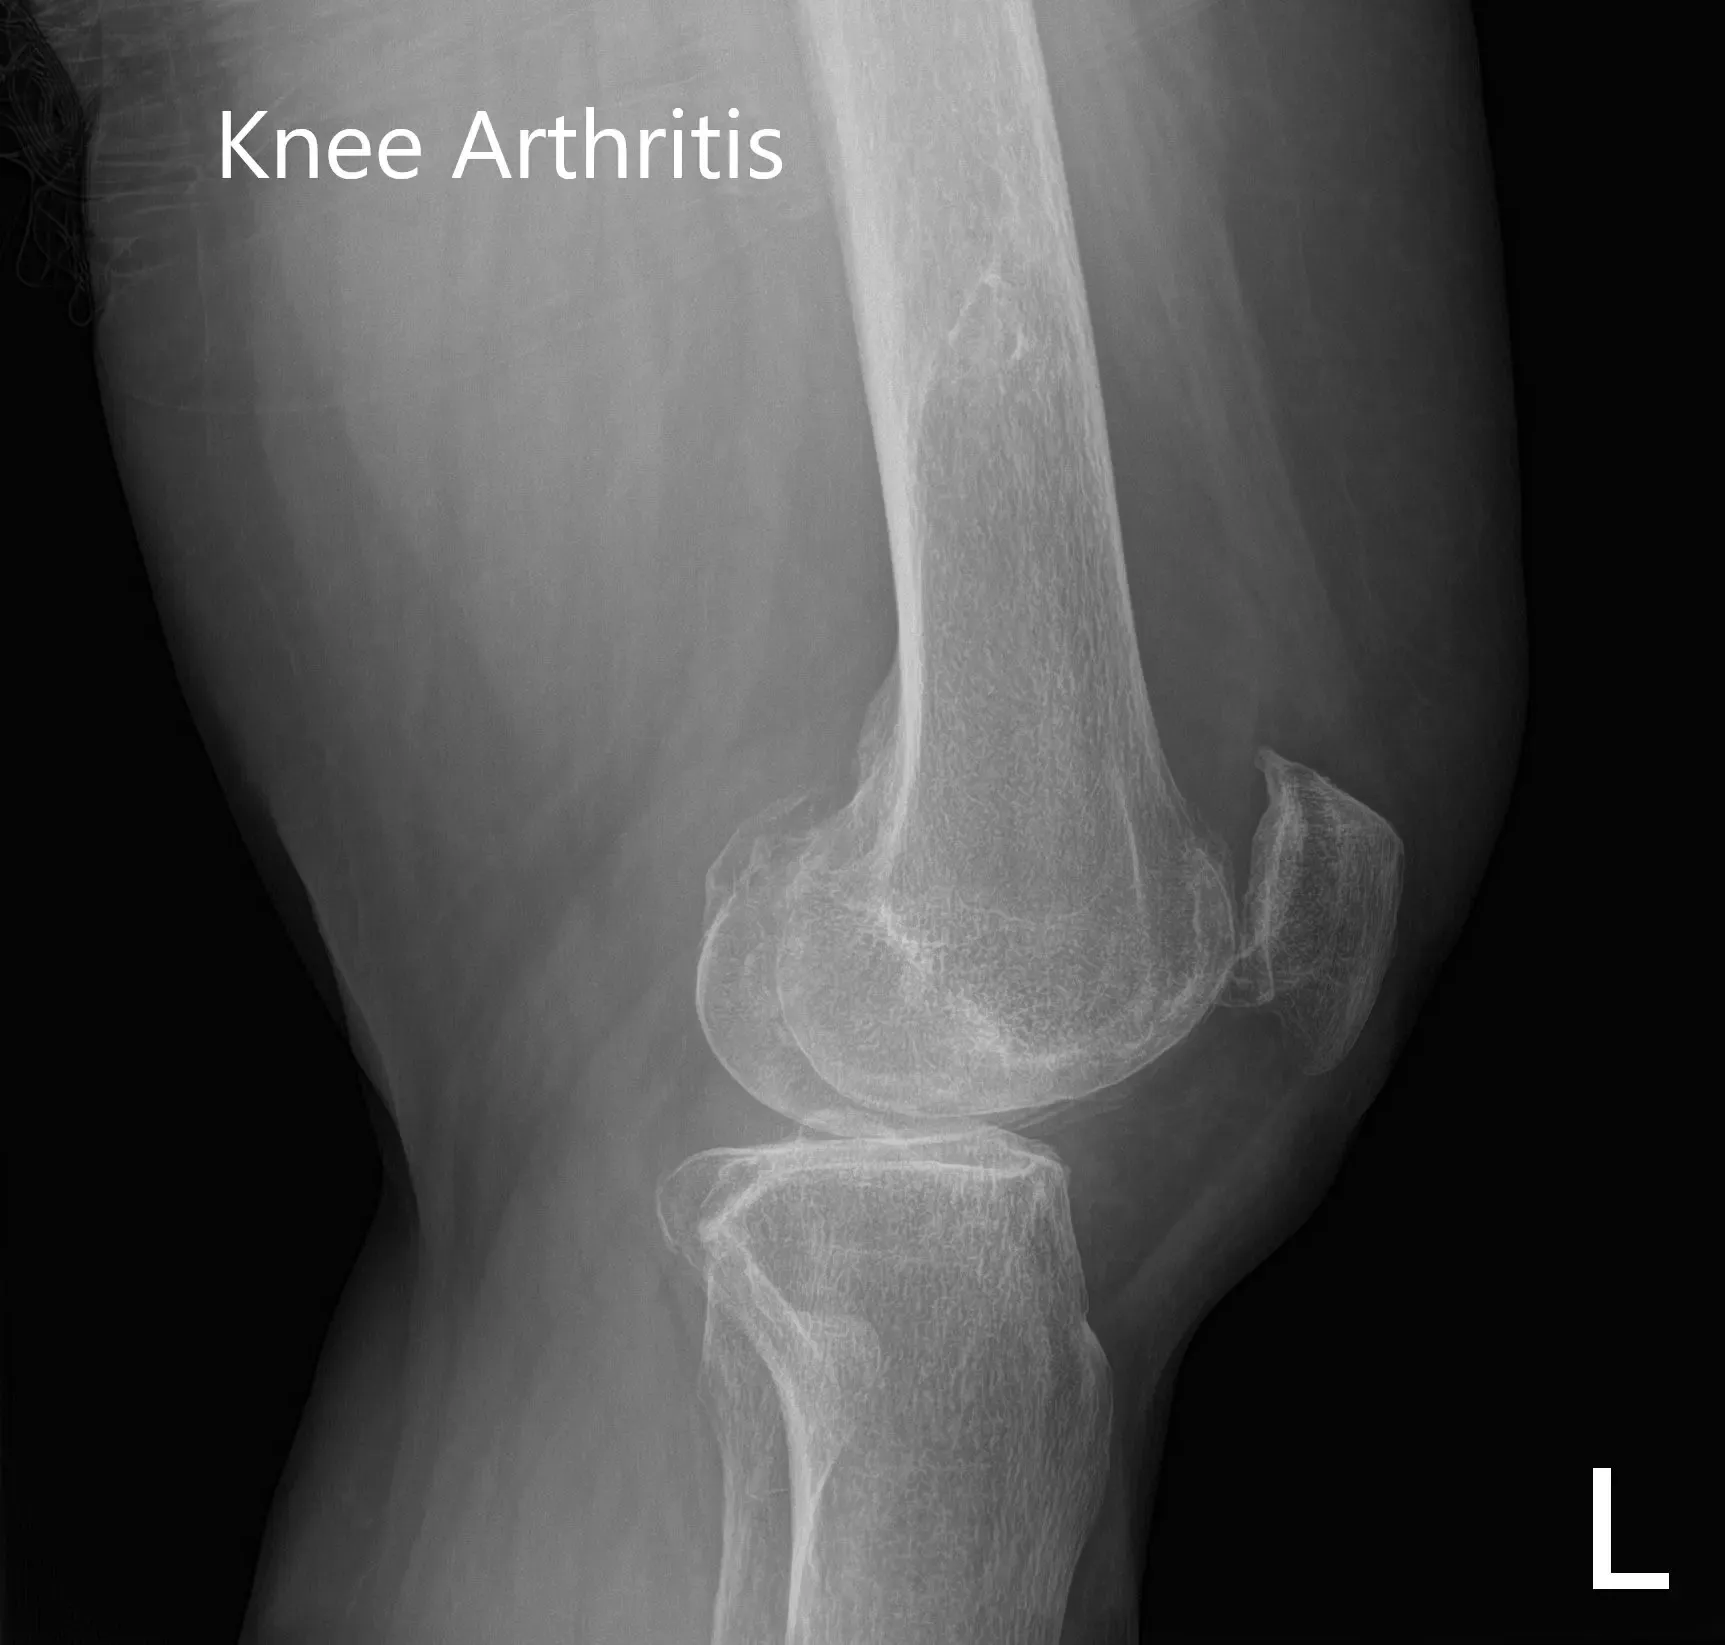

Estaba estresado por el dolor que últimamente había empezado a perturbar su sueño. Dijo que el dolor limitaba el estilo de vida. Los estudios de imagen revelaron osteoartritis tricompartmental severa. Se discutieron en profundidad con el paciente diversas opciones de manejo no quirúrgico y quirúrgico. Se le consideró candidato para un reemplazo total personalizado de rodilla izquierda.

Radiografía preoperatoria que muestra imágenes AP e laterales de la rodilla izquierda